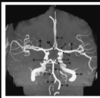

Name the labelled structures

A- left vertebral artery

B- Right vertebral artery

C- Right anterior inferior cerebellar artery (AICA)

D- Basilar artery

E- Superior cerebellar artery

F- Left posterior cerebral artery

G- Arrowhead on R ICA.

H- L ICA

I- L ICA bifurcation into ACA and MCA

J- Left ACA

K- Left MCA

L- ACA

M- AComm

N- Bifurcation of R MCA

The PICA normally branches off the distal part of the vertebral arteries